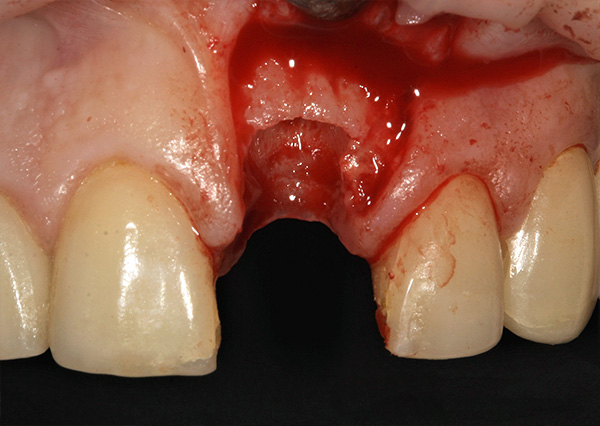

Em seguida, o retalho gengival é cortado e reclinado, um implante é inserido no orifício e o material ósseo granular é introduzido para a regeneração óssea: